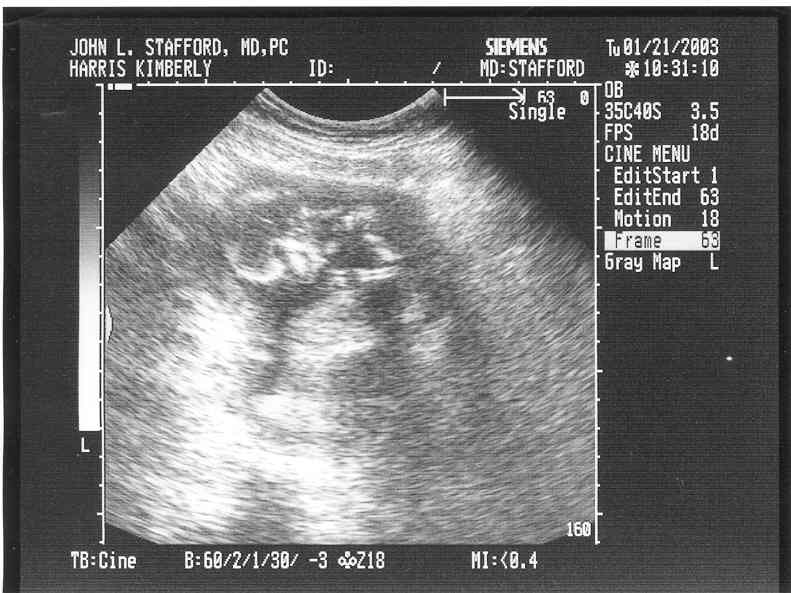

Ultrasound Pictures at 14 weeks, 2 days pregnant!

This one is a little harder to see. The head is on the left and the bright white lines are the legs. You can kind of make it out from that!